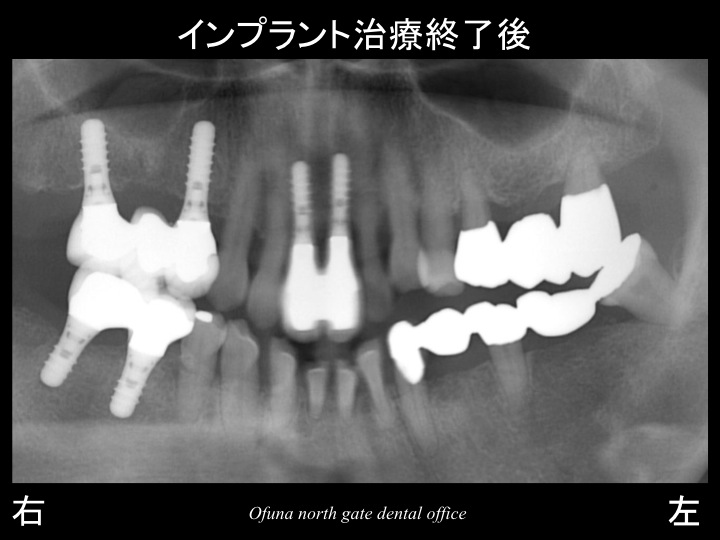

以下がインプラント治療が終了した状態です。

今回の症例のテーマは、『治療計画の難しさ』でした。